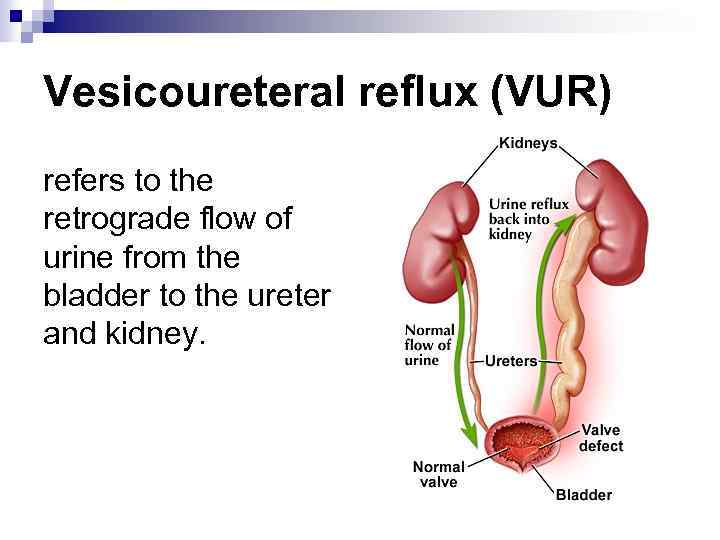

Vesicoureteral reflux (VUR) refers to the retrograde flow of urine from the bladder to the ureter and kidney.

Vesicoureteral reflux (VUR) refers to the retrograde flow of urine from the bladder to the ureter and kidney.

Vesicoureteral reflux (VUR) VUR is present in 35% of children with UTI. VUR predisposes to infection of the kidney (pyelonephritis) by facilitating the transport of bacteria from the bladder to the upper urinary tract.

Vesicoureteral reflux (VUR) VUR is present in 35% of children with UTI. VUR predisposes to infection of the kidney (pyelonephritis) by facilitating the transport of bacteria from the bladder to the upper urinary tract.

Vesicoureteric reflux (VUR) Reflux severity is graded using the International Reflux Study Classification of I to V and is based on the appearance of the urinary tract on a contrast voiding cystourethrogram (VCUG).

Vesicoureteric reflux (VUR) Reflux severity is graded using the International Reflux Study Classification of I to V and is based on the appearance of the urinary tract on a contrast voiding cystourethrogram (VCUG).